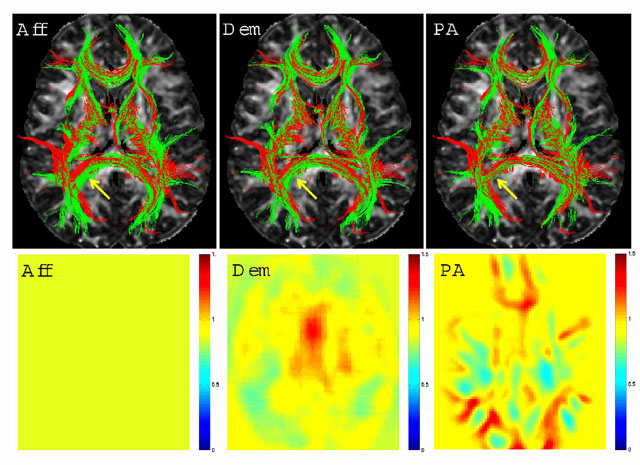

We tested the registration component of this algorithm without updating the clustering with 26 major fiber bundles. The poly-affine warp fields with relatively limited number of components resulted in similar quality registrations when compared with results from a benchmark non-linear registration algorithm that was run on FA images:

Corpus Callosum, Cingulum and the Fornix were selected for further investigation because of the specific challenges they present. These three structures are in close proximity with each other, and that results in many mislabeled fibers when labeled using a high dimensional atlas (see figure below (left)). Their close proximity also results in a number of trajectories deviating from one structure to another. These are precisely the sorts of artifacts we wish to reduce through learning common spatial distributions of fiber bundles from a group of subjects.

We also constructed two different atlases to compare the effects of labeling algorithms on the quality of resulting group maps. The first one is constructed using the initial labels from the high dimensional atlas. A second one is built using the proposed algorithm: